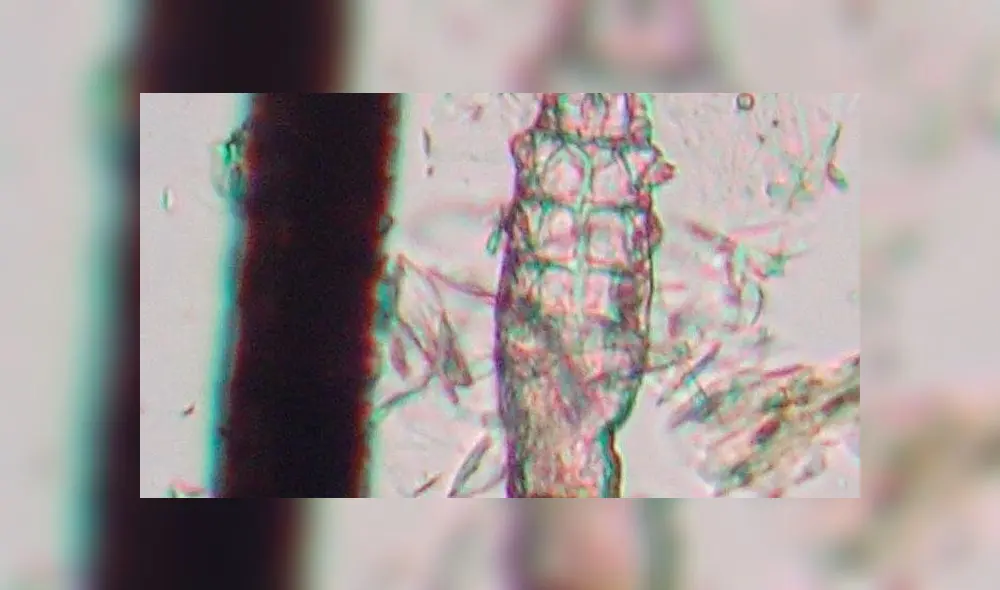

Demodex: el ácaro que vive y se reproduce en el rostro ¿es una amenaza?